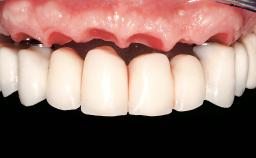

Immediate Loading of Six Implants in the Mandible and Six Implants in the Maxilla and Final Restoration with Full-Arch CAD/CAM Metal Framework FDPs Involving Digital Planning and Guided Surgery

Abutment Type CAD/CAM

Prosthesis Type FDP

Defining Characteristics Fully edentulous upper jaw to be rehabilitated with an implant-borne fixed dental prosthesis

Retention Screw-retained, with 4 or more splinted implants Screw-retained, with 4 or more splinted implants